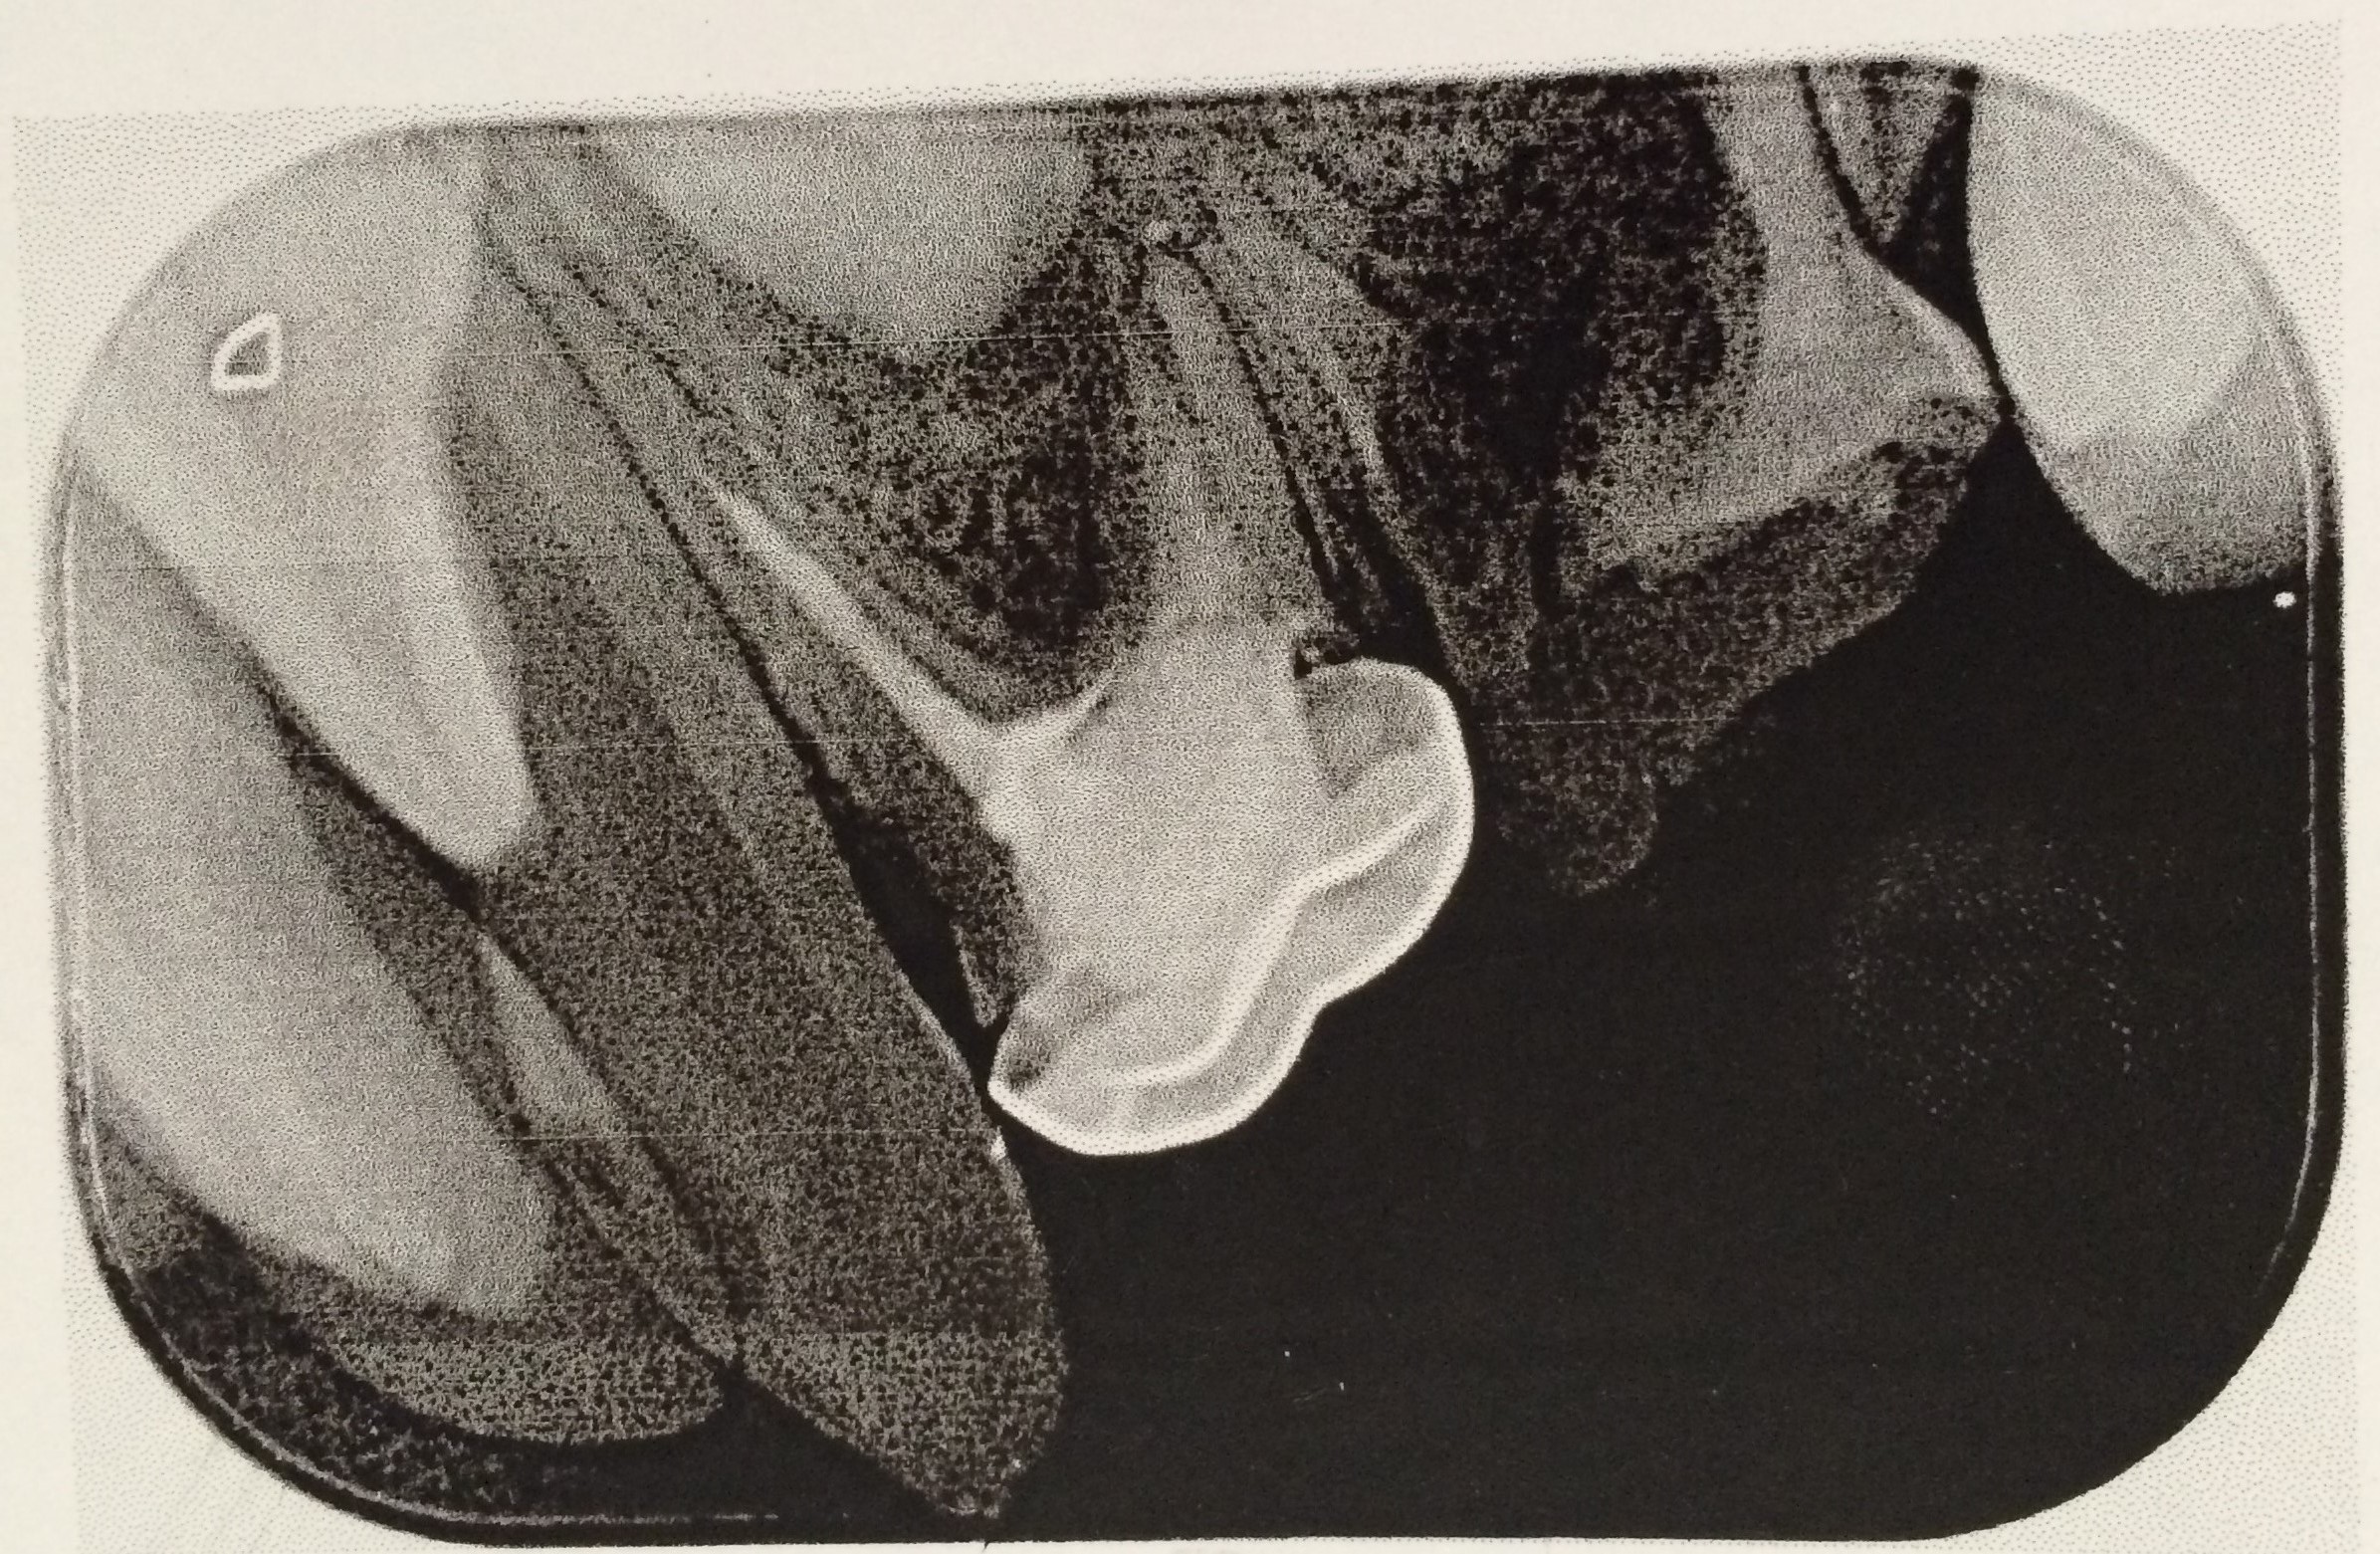

Perforasi iatrogenik merupakan salah satu resiko yang sering terjadi dalam perawatan endodontik yang disebabkan oleh kesalahan operator. Perforasi dapat terjadi pada apeks, lateral atau korona. Perawatan untuk perforasi dapat dilakukan dengan bedah atau non bedah. Prognosis dari perforasi endodonti dipengaruhi oleh beberapa faktor antara lain adalah waktu terjadinya perforasi, lokasi perforasi dan besarnya perforasi. Tujuan laporan kasus ini untuk melaporkan perawatan perforasi korona pada pulpektomi gigi decidui. Kasus seorang anak laki-laki usia 6 tahun datang bersama ibunya dengan keluhan gigi bawah belakang kanan sering sakit tiba-tiba sejak tiga bulan yang lalu. Diagnosis pada gigi molar pertama kanan rahang bawah adalah karies profunda kelas I dengan pulpitis irreversible. Perawatan yang dilakukan adalah pulpektomi. Dalam proses perawatan terjadi perforasi korona di mesial yang disebabkan oleh trauma bur preparasi saat dilakukan pembukaan atap pulpa. Perawatan pulpektomi tetap dilanjutkan dengan menutup daerah perforasi dengan zinc phosphat cement dan diakhiri dengan tumpatan tetap stainless steel crown (SSC). Kesimpulan dari laporan kasus ini yaitu perawatan perforasi korona dengan non bedah pada pulpektomi gigi decidui mempunyai prognosis yang baik. Perawatan dilakukan dengan bahan tumpatan yang memiliki ketahanan terhadap saliva dan tidak mengiritasi pulpa ataupun gingiva.